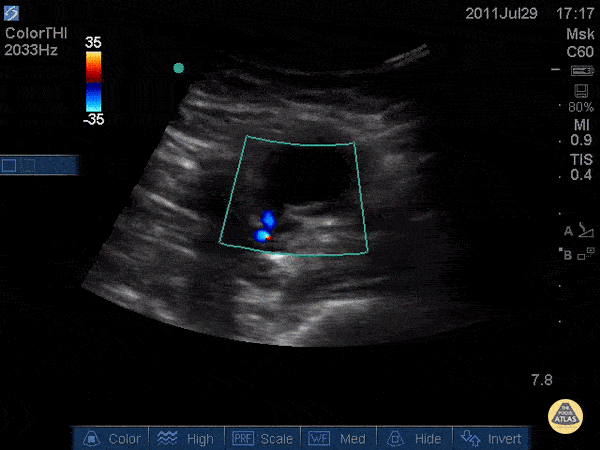

Vascular - Pseudoaneurysm - "Thar She Blows"

WCUME 2017 Submission for "Best POCUS" Thought this was an abscess and almost cut into it. POCUS saved me. Russell Horowitz, MD - Northwestern